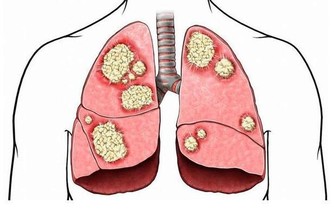

免疫力降低

侵入人體的細菌及病毒要由體內的白血球來對抗,但每當體溫降低1℃,白血球所提供的免疫力便會減少37%,因此體溫較低的人,在季節交換時比較容易感冒。